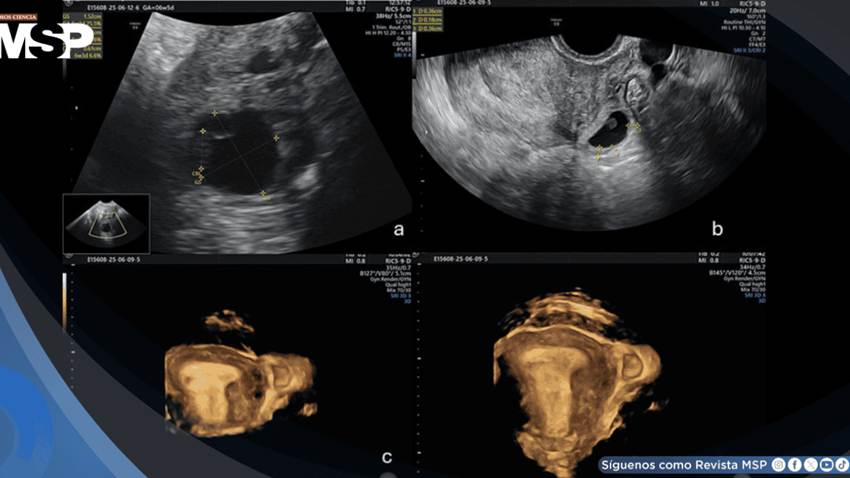

La evaluación ecográfica transvaginal reveló hallazgos diagnósticos inequívocos de embarazo intersticial. Se identificó un saco gestacional que medía 15,5 por 14 milímetros, conteniendo un embrión viable con longitud cráneo-caudal de 3,7 milímetros, consistente con edad gestacional de seis semanas.

El elemento más preocupante fue la ubicación anatómica del saco gestacional en la porción intersticial de la trompa de Falopio izquierda, completamente separado de la cavidad endometrial y rodeado por una capa miometrial peligrosamente delgada de menos de cinco milímetros de espesor.

Estos hallazgos cumplían todos los criterios diagnósticos de Timor-Tritsch para embarazo intersticial. El endometrio presentaba un grosor de 15 milímetros, y el útero mostraba evidencia de fibromatosis. Afortunadamente, no se observó líquido libre en la cavidad pélvica, lo que indicaba ausencia de ruptura en ese momento.